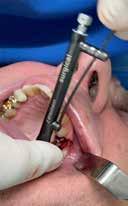

A részleges extrakció befejezése után következhet az implantátumágy preparálása a gyártó utasításai szerint (6.

kép). A bemutatott esetben Nobel Replace CC 4,3x13mm implantátumot helyeztünk be, amely a bukkális oldalon direkt kontaktusba került a megmaradt foggyökérdarabbal (7. kép). Az alveolus oldalfalai és a körszimmetrikius implantátum közötti hézag kitöltésére bovin eredetű xenograftot (Creos S xenogain) használtunk (8. kép). A hasonló

A behelyeztt implantátum primer stabilitását megfelelőnek ítéltük (kb. 40 Ncm) az azonnali terheléshez (9. kép).

6. kép: Implantátum-ágy preparáció. 7. a–b. képek: Implantátum behelyezés. 8. kép: A behelyezett implantátum. 10. a–b képek: Azonnali ideiglenes korona készítése. 9. kép: Megfelelő primer stabilitás.